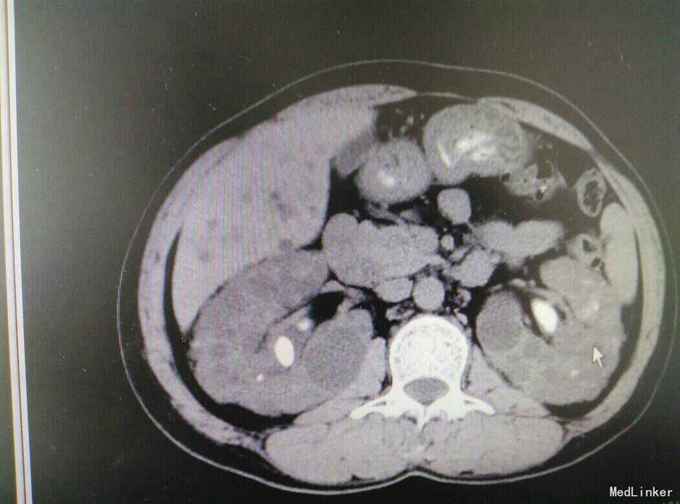

多囊肾合并双肾结石并积水

肾结石 多囊肾 多囊肝

患者47岁,男,因‘’腰痛伴、血尿伴发热7天‘入院。 患者既往有‘高血压’病史多年,7天前无明显诱因出现腰痛,随后出现肉眼血尿,为程肉眼血尿,当天晚上出现发热,最高体温38.6摄氏度,予以对症处理后,发热可退去,但症状反复,患者为求进一步进一步治疗遂来我院。

多囊肾,双肾结石,多囊肝,高血压